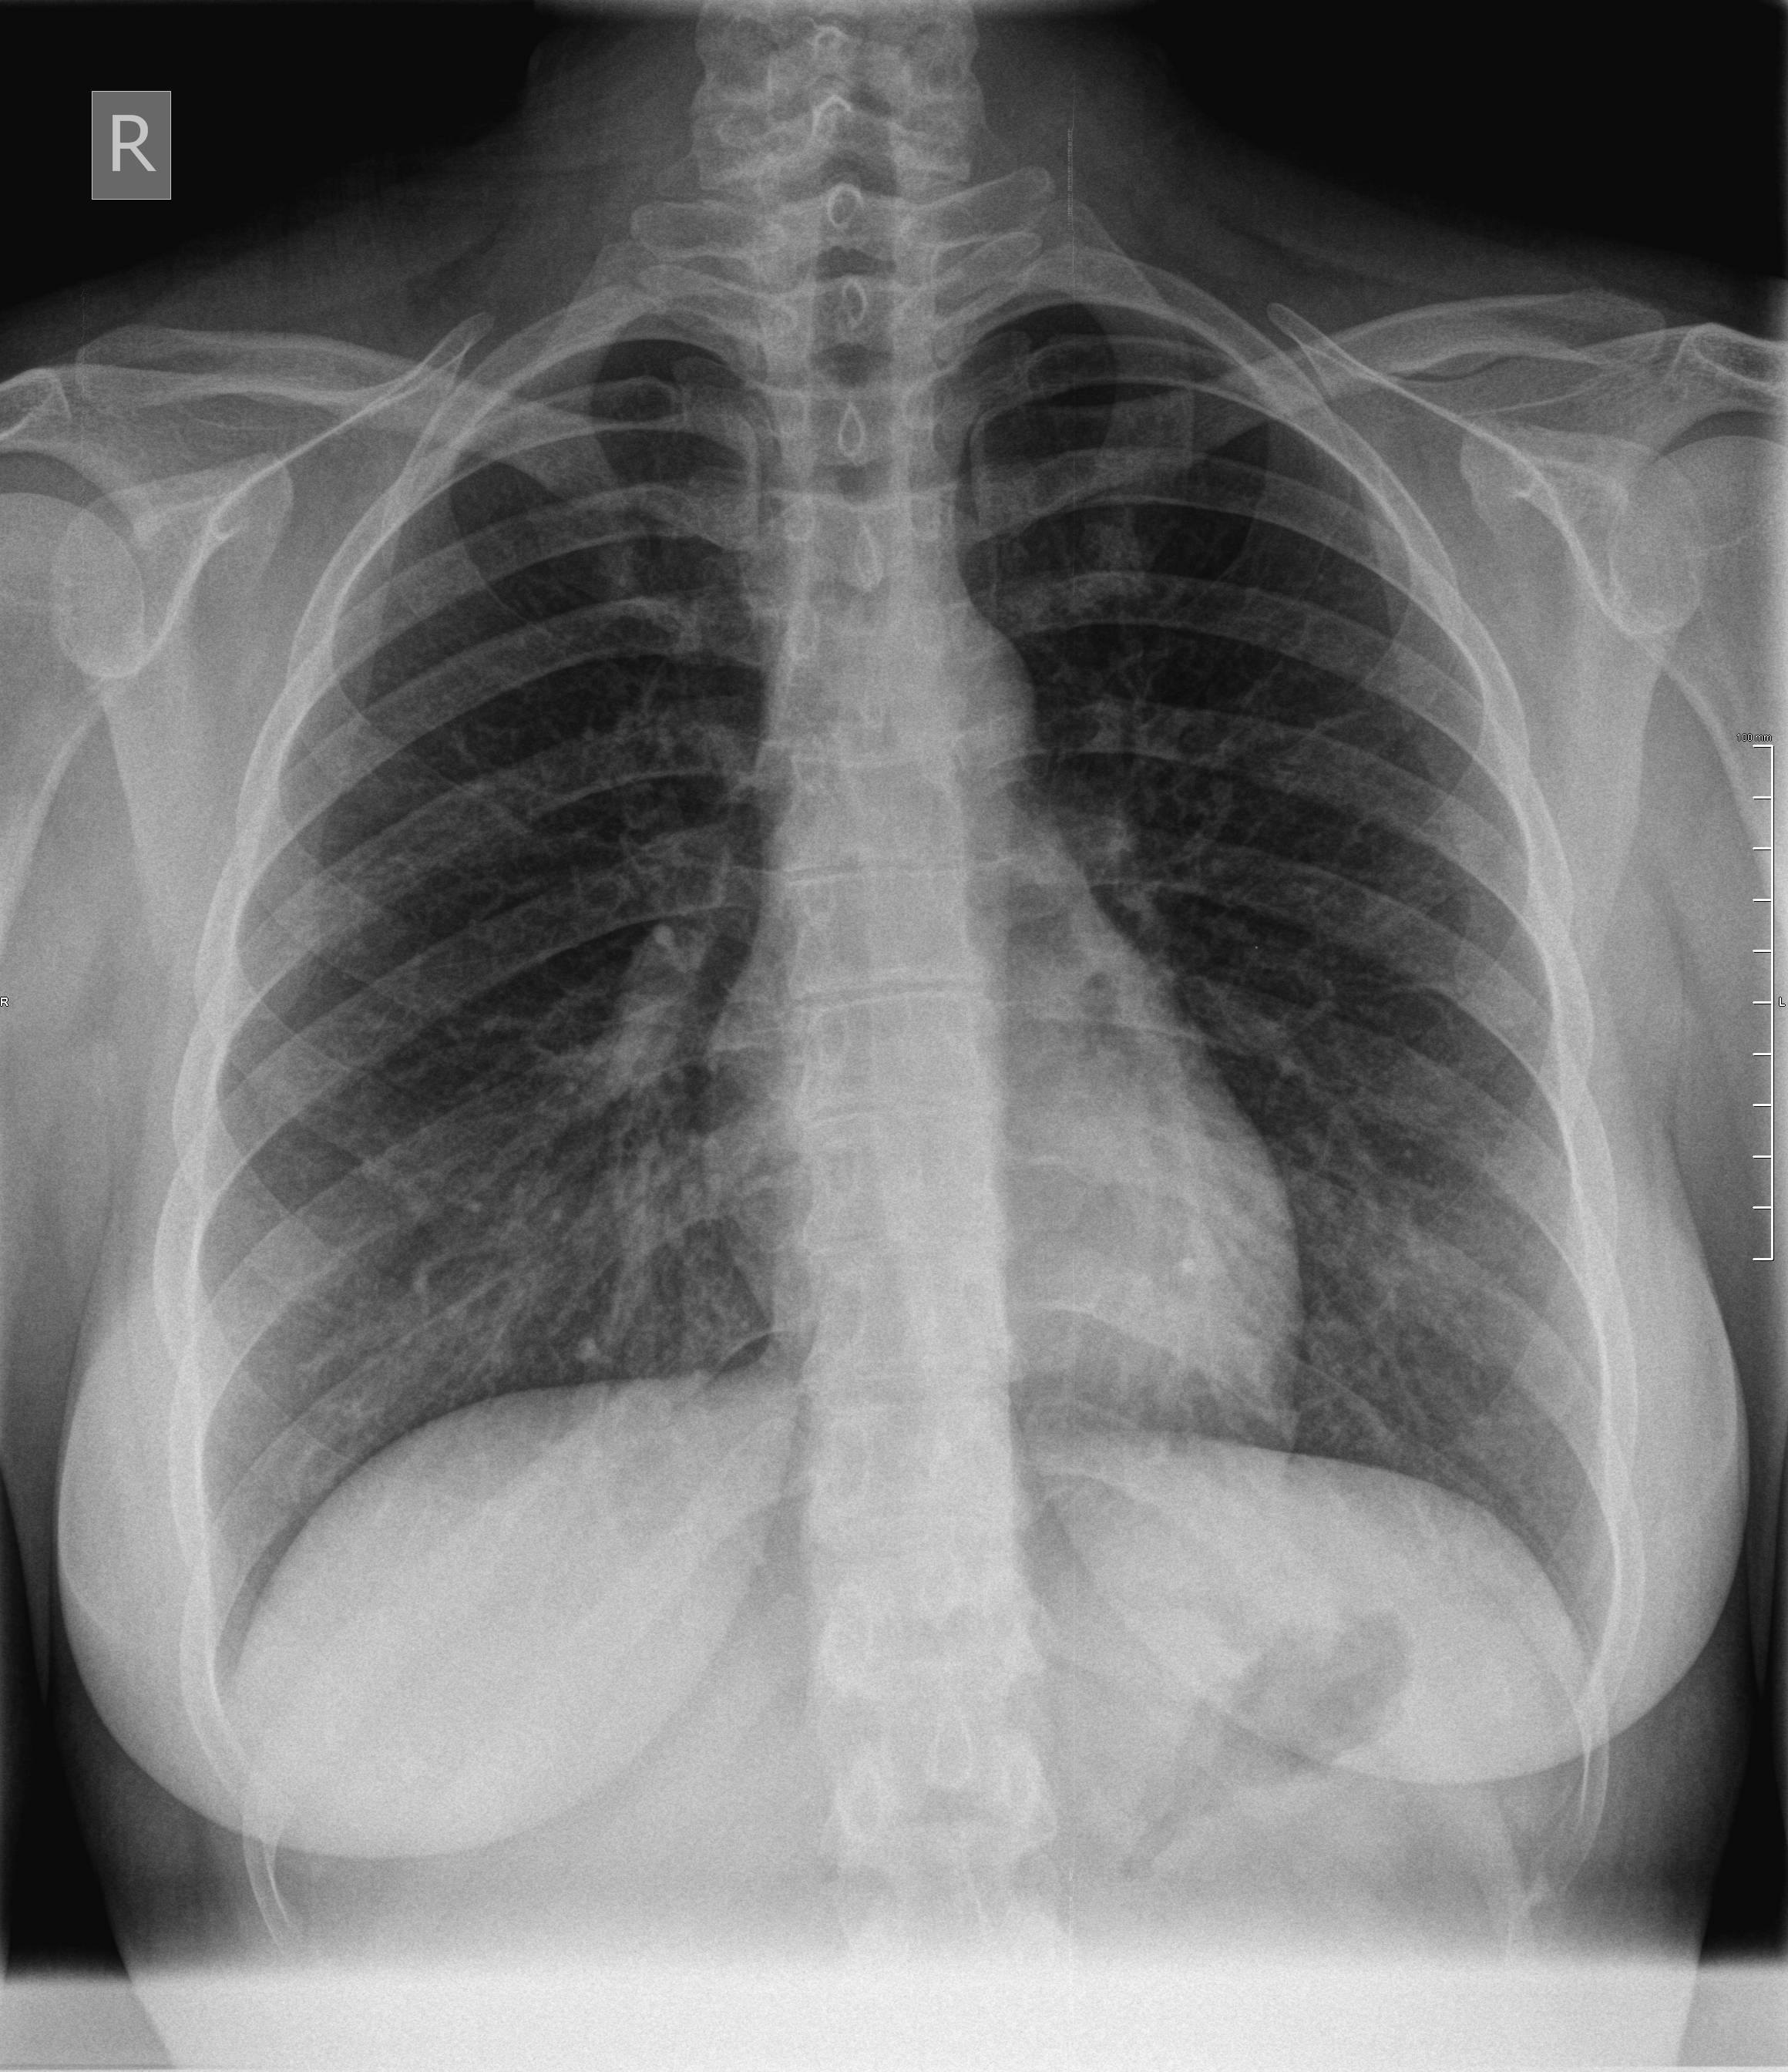

Röntgenaufnahmen des knöchernen Thorax undoder seiner Teile. Der Röntgen-Thorax dient der orientierenden Erstdiagnostik vor allem bei Pneumonie Krebs und chronisch-obstruktiver Lungenerkrankung COPD. Glatt konturiertes normal gewölbtes Zwerchfell in regelrechter Lage Zwerchfellrippenwinkel frei.

Aufnahmen des knöchernen Thorax in mindestens 2 Ebenen. Bei uns in der Klinik ist es langsam zur Gewohnheit geworden Röntgen Thorax in einer Ebene anzufordern obwohl die Patienten nicht im Bett liegen. Hierbei handelt es sich um zwei Aufnahmen die aus verschiedenen Richtungen Ebenen gemacht werden. Ein Röntgen-Thorax gehört für viele medizinische Prozeduren zB. Aufnahmen seiner Teile in mindestens zwei Ebenen Abrechnungsbestimmung. Das sehen wir gleich. Große Bullae rechts Thorax-CT Pleurosis calcarea rechts Thorax pa Pleurosis calcarea links. Aufnahmen des knöchernen Thorax in mindestens 2 Ebenen. Dies ist ein unauffälliger Normalbefund einer Röntgen-Thorax-Aufnahme.

Normalbefund und krankheitstypischer Befund. Sollten Röntgenaufnahmen des Thorax wenn möglich immer in posterior-anterior Strahlengang erfolgen da das Herz ansonsten zu groß dargestellt wird. Normalbefund und krankheitstypischer Befund. Aufnahmen seiner Teile in mindestens zwei Ebenen Abrechnungsbestimmung. Weitere Indikationsstellungen siehe Leitlinien für die Überweisung zur Durchführung von bildgebenden. 3543 FFA mindestens 150m - 250m Fernaufnahme. 5004 Panoramaschichtaufnahme der Kiefer.